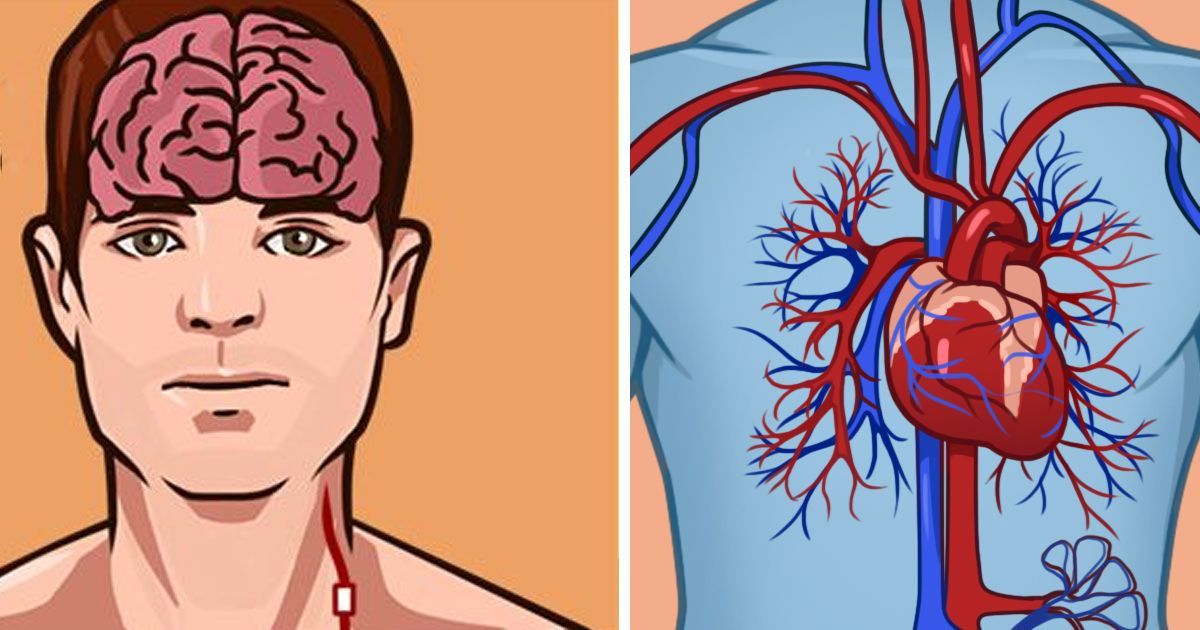

Is it a stroke or a heart attack? How to tell the difference